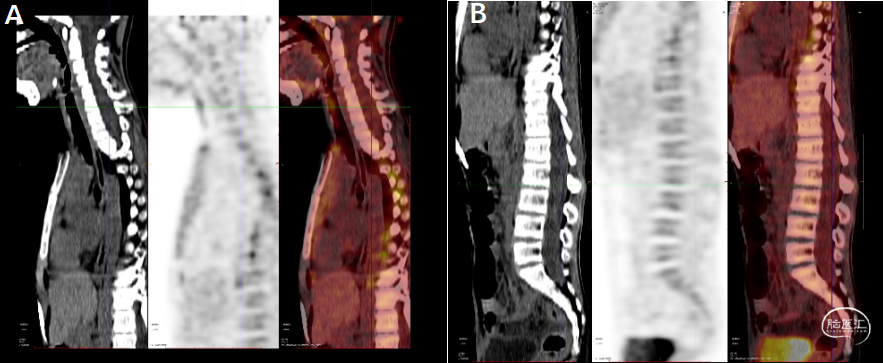

影像资料(PET-CT:2025-11-25)详见下图

A-B:延髓及颈髓前方条状低密度影,伴少许FDG摄取;颈髓及下胸段脊髓FDG摄取下降;腰段椎管腔内弥漫性少许FDG摄取,可符合感染性病变可能